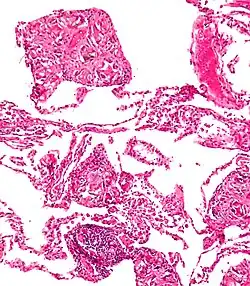

Peritoneum

Foreign bodies in the peritoneum can include retained surgical instruments after abdominal surgery. Rarely, an intrauterine device can perforate the uterine wall and enter the peritoneum.

Foreign bodies in the peritoneum eventually become contained in a foreign body granuloma. In the extremely rare case of retained ectopic pregnancy, this forms a lithopedion, which involves the fetus being too large to be reabsorbed, and is calcified[13] as a means of shielding the surrounding tissue from infection.